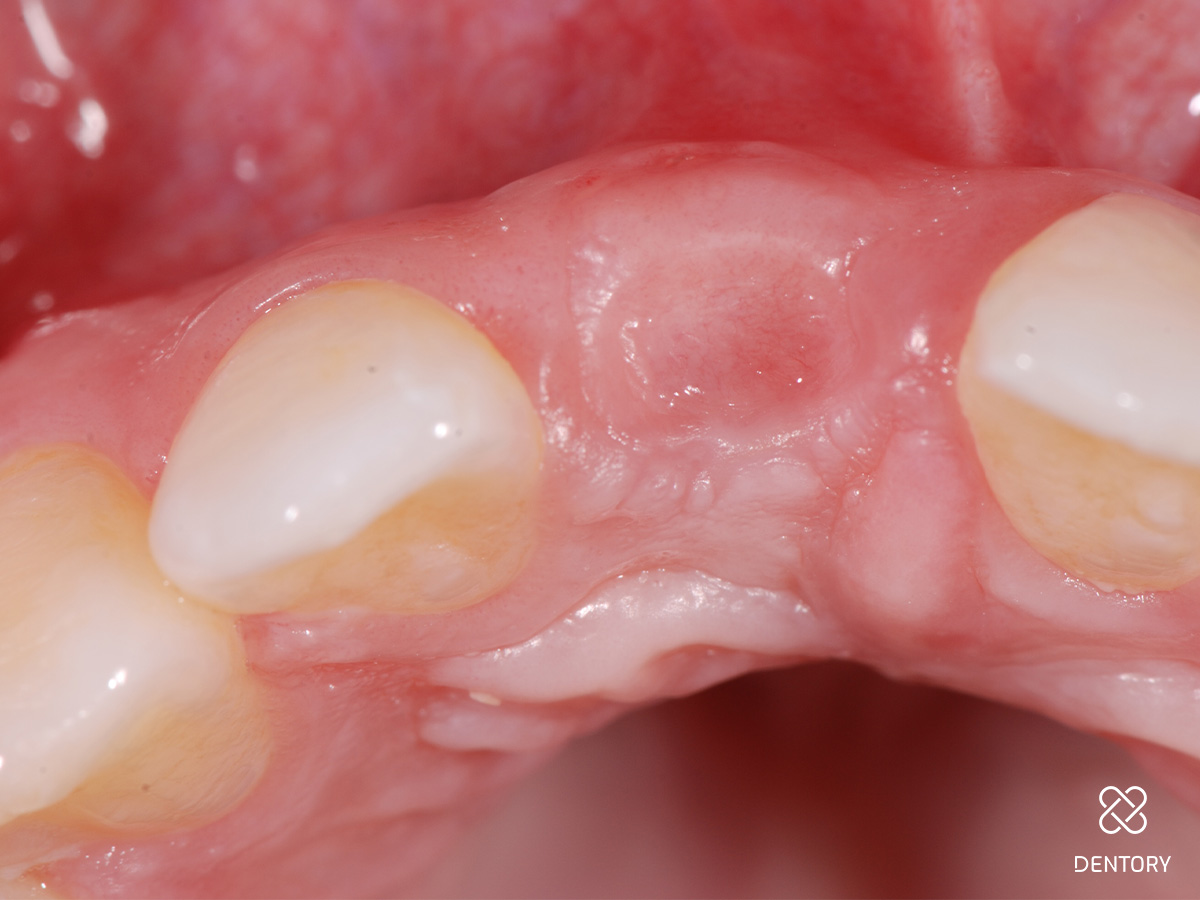

Abbildung 15

Nach 18 Tagen wurde mit der Ausformung der Weichgewebe begonnen. Nach Punch-Grafts kommt es gelegentlich zu Einziehungen auf der vestibulären Seite; diese können mit einem groben Diamanten korrigiert werden.